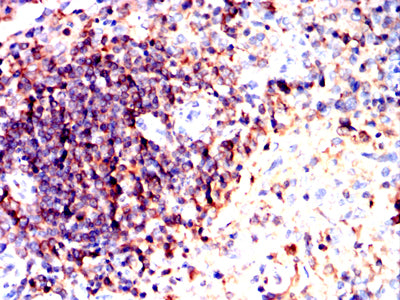

Immunohistochemical analysis of paraffin-embedded Rabbit spleen tissues using ATM mouse mAb with DAB staining.

鄂公网安备42018502007531号